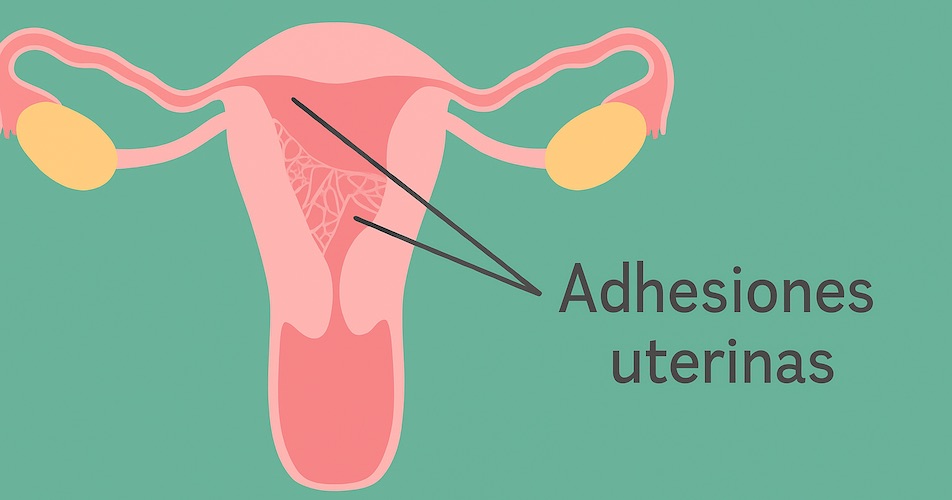

🔬 Adhesiones intrauterinas (Síndrome de Asherman)

Las adhesiones intrauterinas son bandas de tejido fibroso que se forman dentro de la cavidad del útero, provocando que sus paredes se adhieran parcial o totalmente. Esta condición puede alterar la anatomía uterina normal y afectar la menstruación, la fertilidad y la salud reproductiva.

Estas agresiones pueden generar una cicatrización anormal, dando origen a las adherencias.